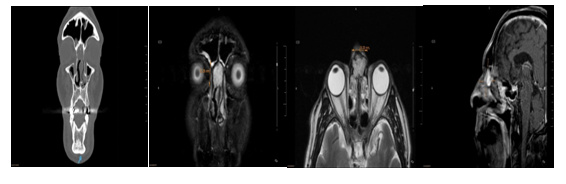

It was not necessary to perform an external approach, nor did they receive blood transfusions during or after the surgery. The patient with the tumor located in the posterior ethmoid was operated by the endonasal approach and the vascular pedicle was controlled prior to the resection of the tumor by cauterizing the sphenopalatine artery (Figure 3).

The intraoperative histological study was reported as a vascular tumor without atypia and the deferred histopatological study as a cavernous hemangioma. The nasal cavity hemangioma was resected by endonasal approach. The intraoperative excisional biopsy was reported as a cavernous hemangioma (Figure 4). Two had a nasal tamponade that was removed at 48 hours and in 2 a hemostatic matrix was used (surgifló). The length of stay was 24 hours in three and 48 hours in another. There were no complications. The follow-up was greater than 5 years in two, 2 years in one and 1 year in another patient. No recurrences were detected.